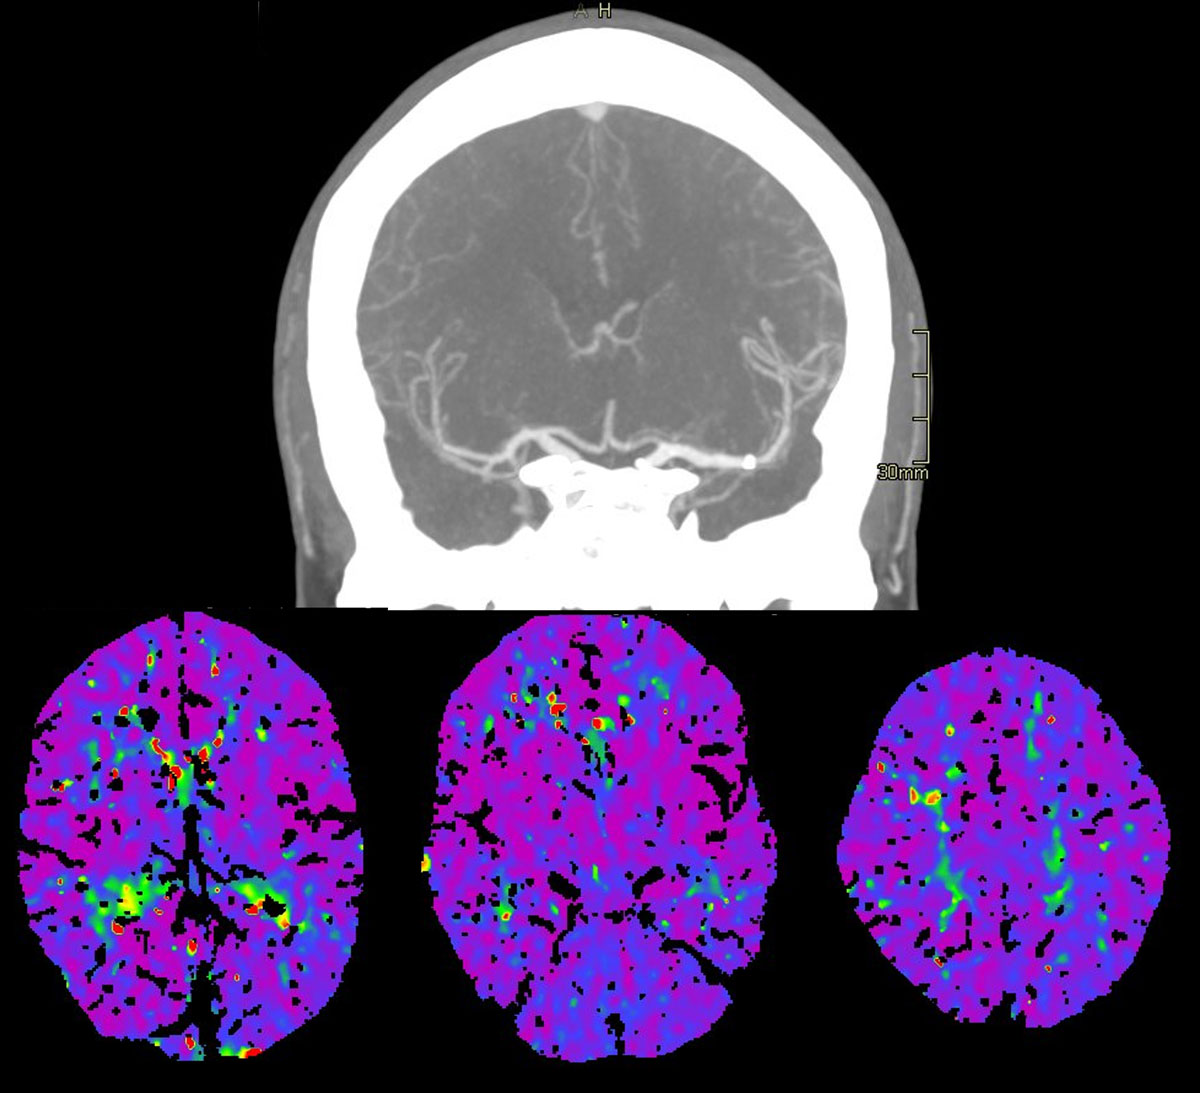

CT – CTA - CTP

This clinical case presents a 28-year-old female patient presenting with a wake-up stroke, managed with endovascular treatment.

• 28 yo, Female

• Wake up stroke (LKW 02.00)

• NIHSS: 15

• No i.v. lysis

• CTA: 10.25